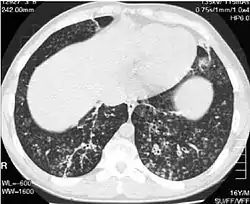

![]() صور تصوير مقطعي محوسب عالي الجودة لأسفل الصدر في ولد عمره 16 سنة مصاب بالتهاب عموم القصيبات المنتشر صور تصوير مقطعي محوسب عالي الجودة لأسفل الصدر في ولد عمره 16 سنة مصاب بالتهاب عموم القصيبات المنتشر | |

يتطلب تشخيص المرض فحص طبي للرئتين ونسيج القصيبات، وهو ما قد يحتاج لخزعة، أو المفضل أكثر تصوير مقطعي محوسب عالي الجودة للرئتين. تشمل المعايير التشخيصية للمرض التهاب شديد في كل طبقات القصيبات التنفسية وإصابات في نسيج الرئة تظهر في شكل عقيدات في القصيبات النهائية والتنفسية في كلا الرئتين. تظهر العقيدات في التهاب عموم القصيبات المنتشر في صورة كتل معتمة عند رؤيتها بالأشعة السينية، وقد تسبب انسداد مجرى الهواء، وهو ما يتم تقييمه بقياس التنفس. تكشف الأشعة السينية كذلك عن اتساع ممرات القصيبات، وهي علامة أخرى للمرض. يُظهر التصوير المقطعي المحوسب عالي الجودة عادة انسداد بعض ممرات القصيبات بالمخاط، وهو ما يشار إليه باسم "علامة شجرة في برعم". نقص تأكسج الدم، وهو علامة أخرى على صعوبة التنفس، يتم اكتشافه عن طريق قياس محتوى الأكسجين وثنائي أكسيد الكربون في الدم، باستخدام اختبار يسمى غازات الدم الشرياني. أشياء أخرى يمكن ملاحظتها في المرض تشمل تكاثر الخلايا اللمفاوية، والخلايا المتعادلة، ومنسجات رغوية في بطانة الرئة. يمكن اكتشاف بكتيريا مثل المستدمية النزلية، والزائفة الزنجارية. يمكن مشاهدة ارتفاع مستوى غلوبيولين مناعي ج، وغلوبيولين مناعي أ، بالإضافة لوجود عامل الروماتويد. قد يحدث كذلك تراص دموي، أي تراص كريات الدم الحمراء استجابة لوجود أجسام مضادة في الجسم. يمكن كذلك اكتشاف الخلايا المتعادلة، والبيتا ديفنسين، واللوكوترايينات، والكيموكين في سائل غسل القصبات والأسناخ.